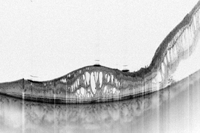

3 fueron los primeros en describir las alteraciones de la retina desprendida: engrosamiento retiniano, separación de las capas intraretinianas y ondulaciones de la retina externa (

Figura 1 y

Figura 2). Por último, Yetik

Figura 1. Desprendimiento de retina crónico. Se observan separaciones en las capas intraretinianas (Topcon SS-OCT DR-1).

Figura 2. Desprendimiento de retina agudo. Se observan ondulaciones de la retina externa (OLU) (Topcon SS-OCT DR-1).